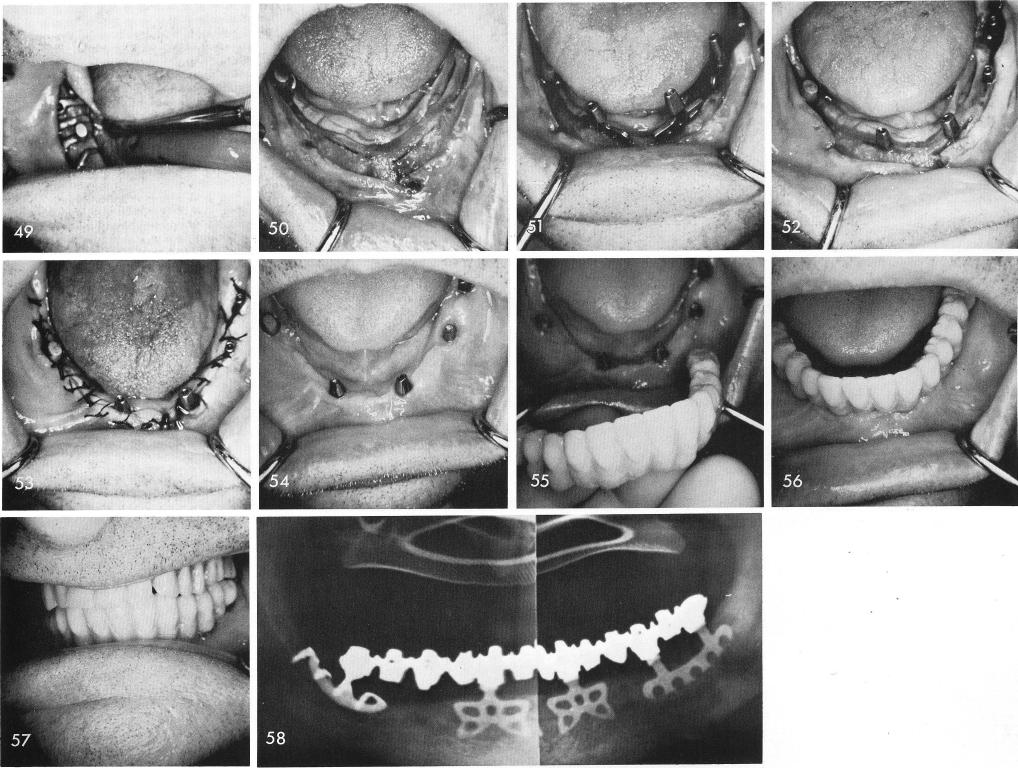

than a partial full arch splint in a totally edentulous mandible. If for some reason the subperiosteal did not fit the three blades were still inserted. The fit, however, was exact, fig. 49. Grooves were then made symmetrically to one another and to the subperiosteal implant, fig. 50, and the blades were inserted, figs. 51, 52, and the tissues closed, fig. 53. Healing again shows to be excellent even with the Vitallium subperiosteal implant and the titanium bladevents, fig. 54. Because of vertical bone loss anteriorly the finished restoration contained a pink gingival portion which ended at the gingival portion of the blades and did not overlap the soft tissues, figs. 55, 56, 57. The post-operative x-ray, fig. 58.

1 Exact fit of subperiosteal implant with bladevent implants in mandible